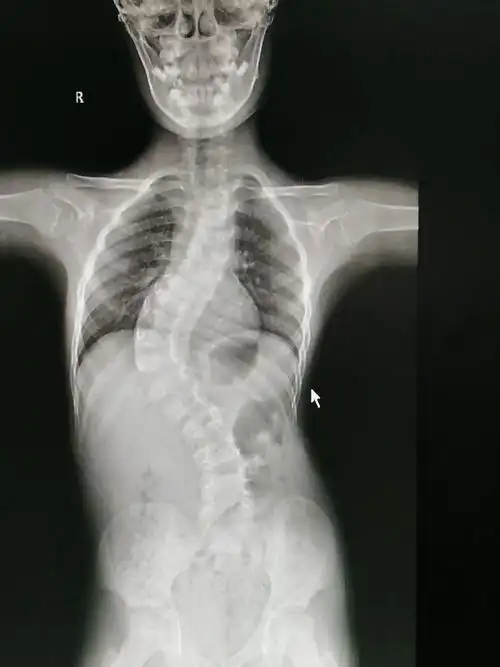

先天性脊柱侧凸站立位全脊柱正侧位:胸椎右侧弯,cobb角53°(t2-t7),t3

最近完成的一例特发性脊柱侧弯

12岁女孩脊柱侧弯曲超过60度,手术矫正后"长高"4厘米